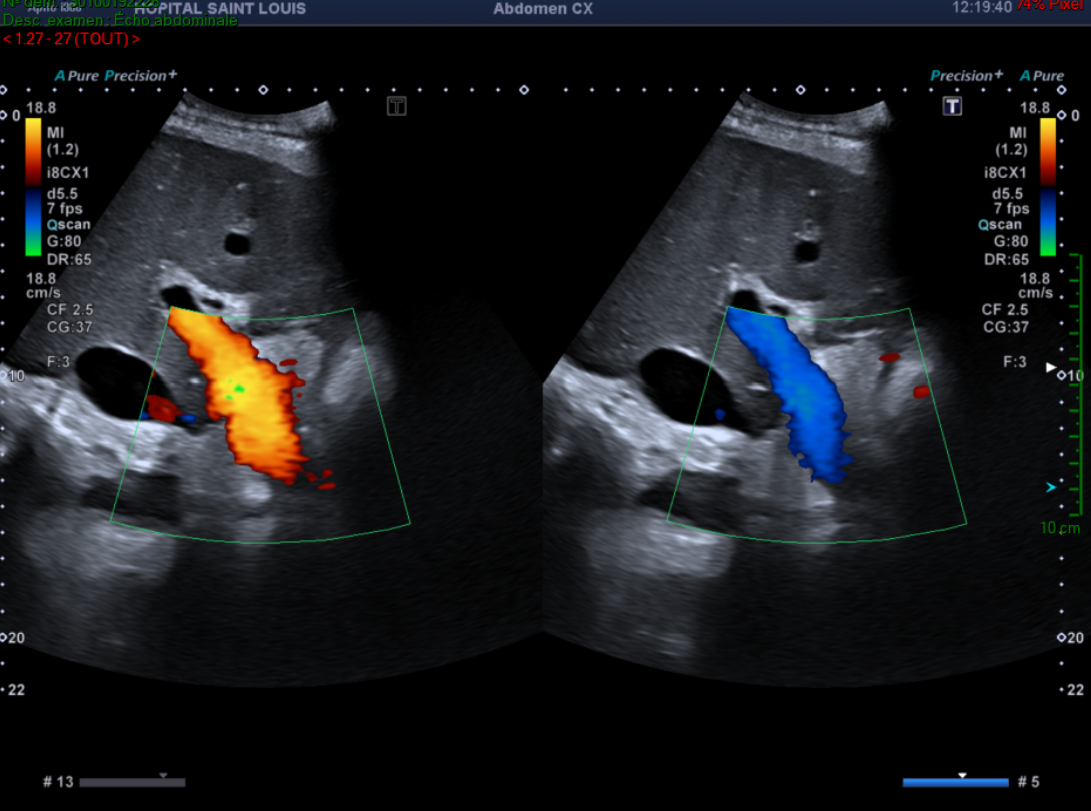

Une perte du flux triphasique des veines hépatiques.

Ces signes échographiques associés aux signes cliniques et biologiques doivent faire suspecter un foie cardiaque.

Le patient sera adressé à un cardiologue qui complètera l’examen par une échographie cardiaque, qui révèlera une insuffisance cardiaque droite sévère.

Ainsi un foie cardiaque est diagnostiqué selon la triade suivante :

• Clinique :

Hépatomégalie douloureuse et signes d’insuffisance cardiaque droite

• Biologie :

Cholestase (PAL, GGT, bilirubine augmentées) et cytolyse modérée

• Echographie Doppler :

Hépatomégalie

VCI dilatée non compliante

Pulsatilité du tronc porte

Perte du flux triphasique des veines hépatiques

Dilatation des veines hépatiques

Ascite

Devant un bilan de cholestase sans dilatation des voies biliaires, et la présence de ces signes échographiques, l'échographiste doit toujours orienter le patient vers un cardiologue.